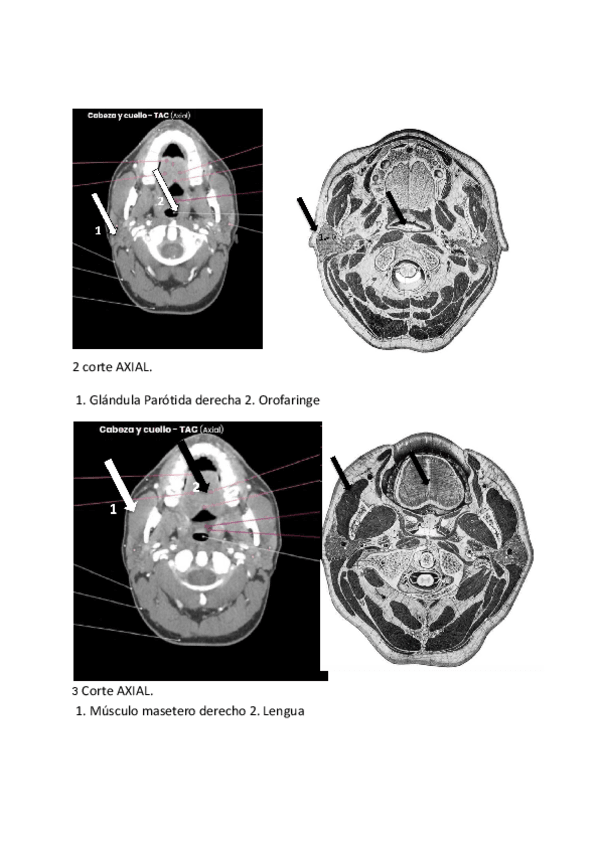

He publicado nuevos practicas de 2º Anatomía: sangre, sistema cardiovascular y respiratorio: Practica-Aplicaciones-readiologicas.pdf

14 páginas